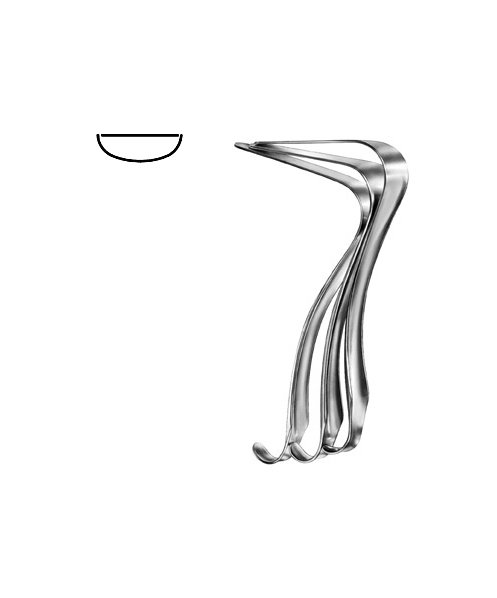

- Gynecology, Surgical Instruments

Endocervical Speculum

- Size : 25 CM - 9 3/4"

- Read more

-

- Gynecology, Surgical Instruments

Endocervical Speculum

- Size : 34.5 CM - 13 1/2"

- Read more